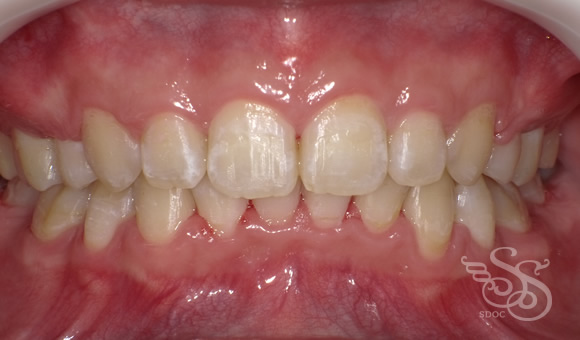

下顎前突(受け口・反対咬合)ClassⅢ

正面:術前

正面:術後

この症例をもっと詳しく見る